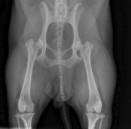

Badaniem można stwierdzić bolesność podczas biernych ruchów w stawie, mniejszy zakres ruchu w stawie, fenomen Ortolaniego – charakterystyczne „klikniecie” w stawie biodrowym wynikające z jego niestabilności. Najdokładniejszym badaniem jest badanie radiologiczne stawów biodrowych. Zdjęcie wykonuję się w projekcji grzbietowo-brzusznej – V-D, pies leży na grzbiecie (niekiedy konieczne jest wykonanie dodatkowych zdjęć w innych projekcjach). W większości przypadków do wykonania takiego zdjęcia konieczne jest uspokojenie pacjenta – sedacja i rozluźnienie mięśni – miorelaksacja, co uzyskuję się za pomocą iniekcyjnych środków farmakologicznych.

Objawy radiologiczne są różne w zależności od stopnia nasilenia zmian w stawie, dotyczyć mogą panewki stawu biodrowego, główki kości udowej lub obu struktur jednocześnie.

Do określenia stopnia dysplazji stosuje się następującą skalę ocen:

A - stawy biodrowe normalne

B - Stawy biodrowe prawie normalne

C - dysplazja nieznaczna

D - dysplazja częściowa (ograniczona)

E - dysplazja ciężka